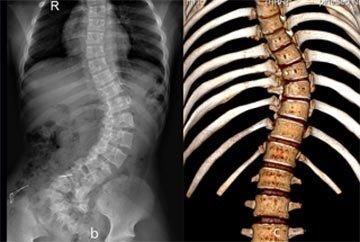

济南中德骨科医院的医生讲述,脊柱侧弯是指脊柱的一个或数个节段在冠状面上偏离身体中线向侧方弯曲,形成一个带有弧度的脊柱畸形,可由多种疾病引起。所以对于脊柱侧弯的治疗也要合理…「查看详情」

脊柱侧弯该怎么办?脊柱侧凸通常发生于颈椎、胸椎或胸部与腰部之间的脊椎,也可以单独发生于腰背部,严重影响患者的健康成长,那脊柱侧弯怎么办呢?…「查看详情」

脊柱侧弯常见于少年,部分原因归结于不良的坐姿,如,身体长期呈扭曲姿势。脊柱侧弯可能引发脊椎病、颈项肌痉挛等疾病,影响心肺功能,以致影响发育等。…「查看详情」